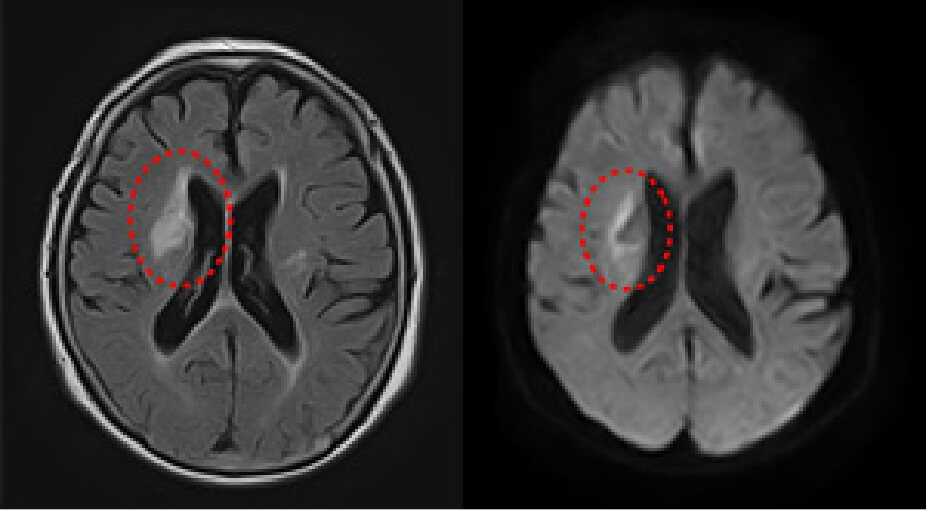

左図と同部位に梗塞のある症例